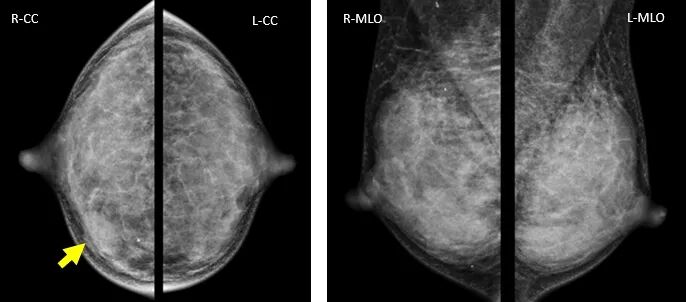

4.不对称性致密影的显示

病例7:查体:未扪及肿块,腺体中R-2D-CC卵圆形不对称致密,DBT显示球形不对称为乳腺正常腺体结构。